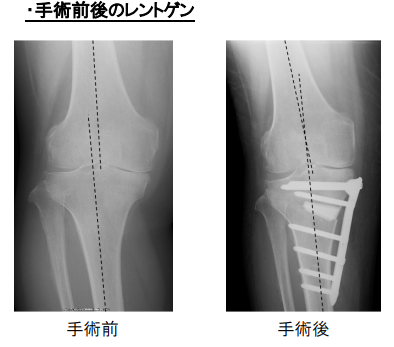

変形性膝関節症、膝関節内の骨壊死に対して施行する人工関節と骨切りの手術は

膝の変形の程度、下肢のアライメント(O脚かX脚か)、膝の可動域、靭帯損傷の有無、患者さんの年齢、体格、活動度などにより手術方法を選択します。

高位脛骨骨切り術はO脚で荷重軸が内 側に傾いており、靭帯(じんたい)などが健康で関節の温存が可能で膝関節の内側だけが悪い場合に、骨を切ってO脚をX 脚に矯正して痛みを取る手術です。適応の条件として、骨がある程度しっかりしていることが必要ですので、おおむね70歳以下で活動性の高い方 が対象となります。ご自分の関節が残りますからスポーツなども可能です し、手術後に万一悪化したとしても、人工膝関節全置換術に移行できるのもメリットです。

人工膝関節単顆置換術は骨の変形が少なく、膝関節の内側(片側)だけ軟骨が傷み、靭帯が健 康な膝関節の片側だけが悪い場合に行われます。た だし耐用年数が全置換術よりも若干落ちますので、目安としては70歳以 上の方が適応となります。痛みを取る確実性は全置換術のほうが高いですが、手術前の膝の屈曲角度は全置換術よりは保てます。前十字靭帯(ぜんじゅうじ じんたい)、後十字靭帯(こうじゅうじじんたい)を切らずに残しますから、 自分の脚に近い感覚も残すことができます。ただし変形が強ければ全置 換術の適応となります。

全置換術は変形性膝関節症が進行して、膝関節全体が悪くなってしまった場合に施行されます。膝関節の全部を人工膝関節に置き 換えますから、高度に破壊された膝の機能を再獲得するのには最も信頼性の高い手術といえます。痛 みを取ることにおいても、耐用年数が15年から20年以上ということを考 えても、長期成績が安定し適応の幅も広い優れた手術だといえます。